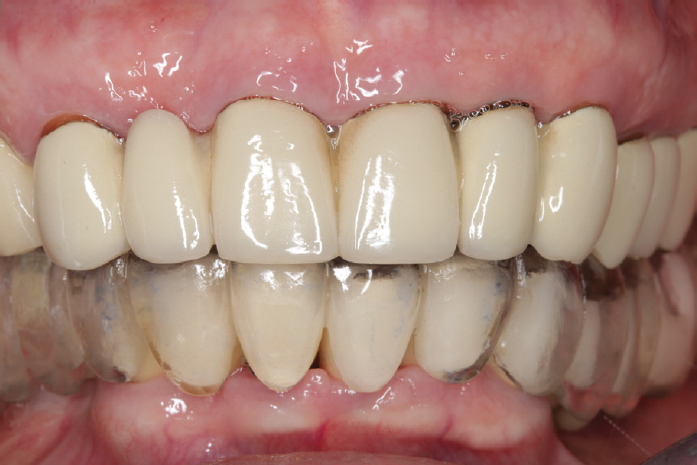

After 4 months of using the temporary structures, the fabrication and fitting of the permanent dentures with tooth and implant support were completed (Fig. 11).

Fig. 11. Permanent metal-ceramic structures based on the teeth and implants: a, anterior projection; b, occlusal projection of the upper dentition; c, occlusal projection of the lower dentition

Рис. 11. Постоянные металлокерамические конструкции с опорой на зубы и имплантаты: a — передняя проекция, b — окклюзионная проекция верхнего зубного ряда, c — окклюзионная проекция нижнего зубного ряда

The patient is currently satisfied with the prosthetics and does not have any complaints related to the masticatory apparatus.